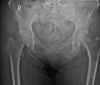

Give a list of differentials in order from most to least likely.

Aggressive in kid = OLEO 1. Osteomyelitis 2. Ewing sarcoma (diaphyseal) 3. Osteosarcoma 4. Lymphoma